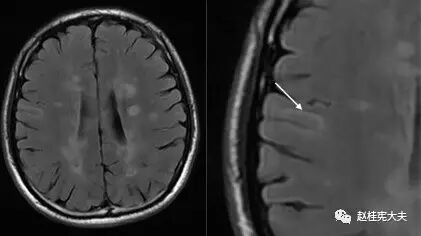

图5. 示双侧放射冠区、侧脑室旁多发圆形、卵圆形或斑片状病灶,T2高信号,部分呈煎蛋征(双娇煎蛋)。(左侧侧脑室旁)病灶长轴与侧脑室长轴垂直。

图8. T2FLAIR像示(左图)上箭头—皮层病灶;(左图)下箭头、(右图)皮层下病灶。

图9. T2 FLAIR像示(右图)皮层下累及U形纤维病灶。

位于脑室周围典型者,长圆形病灶的长轴与大脑或侧脑室长轴垂直,且有一狭窄正常信号带将病灶与侧脑室分开,而之后转为正常表现的低信号提示髓鞘再生;在疾病晚期,病变可发生融合,T2上出现融合性高信号灶,易误为肿瘤;因病灶可沿室管膜静脉从脑室表面进入邻近白质,故胼胝体常首当其冲罹病,且好发于胼胝体内侧或深部,即靠近脑室边缘处。